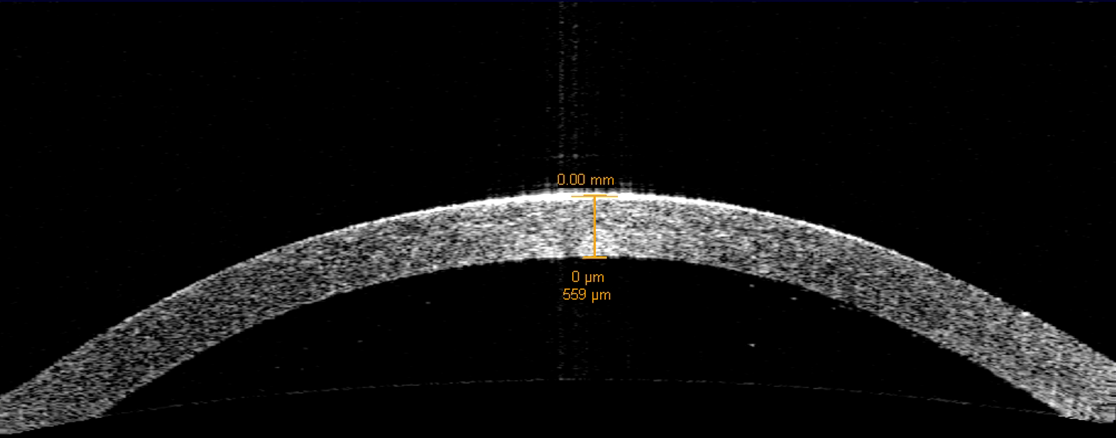

En Qvision, contamos con el equipo OCT, para poder medir cuantitativamente el espesor corneal y controlar sus posibles cambios secundarios al uso de lentes de contacto (edemas, moldeos…). También disponemos del Keratograph que nos mide el menisco lagrimal y sus posibles cambios inducidos por el uso de lentes.

Esta semana os presento un estudio realizado en el Contact Lens & Anterior eye, Assessment of corneal thickness and tear meniscus during contact-lens wear. En él se evalúan los efectos de siete lentes de contacto diferentes sobre el espesor corneal y sobre el volumen del menisco lagrimal, utilizando precisamente la OCT.

Intervinieron 34 pacientes jóvenes portadores de 7 tipos diferentes de lentes de contacto desechables diarias a lo largo de 12 horas de uso, (Delefilcon A, Nelfilcon A, Omafilcon A, Filcon II3, Narafilcon A, Etafilcon A y Hilafilcon B). Se midieron los espesores corneales centrales y periféricos medios así como el volumen del menisco lagrimal más bajo durante las 12 horas de uso en intervalos de 4 horas mediante la OCT. También se midieron después del uso de lentes durante 1 día.

Se observó un pequeño adelgazamiento corneal posterior a las 12 horas de uso de las lentes. La lente Hilafilcon B causó el mayor aumento de espesor en la zona central, mientras que el Etafilcon A lo hizo en la córnea periférica media. Delefilcon A fue la lente que mostró un comportamiento más estable. También se encontró en general, un adelgazamiento del menisco lagrimal, el cual podría ser considerado como motivo de disconfort en el uso. La OCT ofrece la posibilidad de un seguimiento objetivo en el uso de lentes de contacto, aunque en este estudio no se encontraron cambios significativos producidos en el espesor central, sí se muestra la eficacia de esta medida cuantitativa con la OCT de polo anterior.